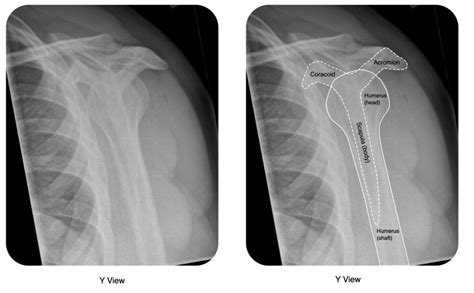

When the X-ray image is developed, the doctor will be looking for several key things. First and foremost, they want to see if the head of the humerus is indeed out of its socket. A normal shoulder X-ray will show the head of the humerus sitting snugly within the glenoid fossa. If it’s dislocated, the humerus will be displaced, often sitting in front of or below the socket. Secondly, they’ll be on the lookout for fractures. Fractures can occur in the humerus itself, the glenoid, or even the clavicle (collarbone), which is closely connected to the shoulder joint. The X-ray can reveal the type and severity of these fractures, which is vital information for planning treatment. Lastly, the X-ray can sometimes show other issues, such as pre-existing conditions like arthritis or bone spurs, which might influence the management of the dislocation. So, it’s a really comprehensive look inside your shoulder!

The primary goal of an X-ray in this scenario is to confirm whether a dislocation has occurred. A normal shoulder joint will show the head of the humerus (the ball) sitting neatly within the glenoid fossa (the socket). When a dislocation is present, the head of the humerus will be displaced, meaning it has popped out of the socket. The X-ray will clearly show this displacement. There are different types of shoulder dislocations, most commonly anterior (where the humerus moves forward) and posterior (where the humerus moves backward). The X-ray will help identify the direction of the dislocation, which is important for guiding treatment. It’s like having a map that shows exactly where the ball has rolled off the track. This visual confirmation is crucial for accurate diagnosis and planning the reduction (putting the shoulder back in place).